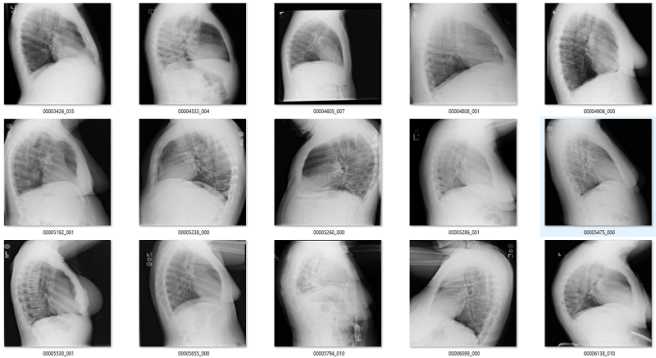

Of the remaining 120 cases, 56 are not frontal chest films. Mostly a mix of lateral films and abdominal x-rays. I would want to get rid of these anyway.

To show that a very small amount of labelled data can be useful, I took the lateral and bad regions films I found using the rotation detector (n = 56), and trained a new model on them. Since I didn’t have very many, I decided to go hog wild and didn’t even use a validation set. Since these tasks are embarrassingly learnable, once it gets near 100% it should generalise well. Obviously there is a risk of overtraining here, but I thought I would risk it.

It worked great! I found an extra couple of hundred lateral films, abdominal films, and a few pelvises.

Obviously if I was building this dataset from scratch it would be easier to solve this part, since I would have access to a lot of relevant non-frontal-chest images. For me to do better than I have now I would need to extract a set of images from a variety of body regions from my local hospital archive, and that is beyond the scope of this blog. So I can’t be sure I got most of these, but it is a pretty good effort from such a small dataset.